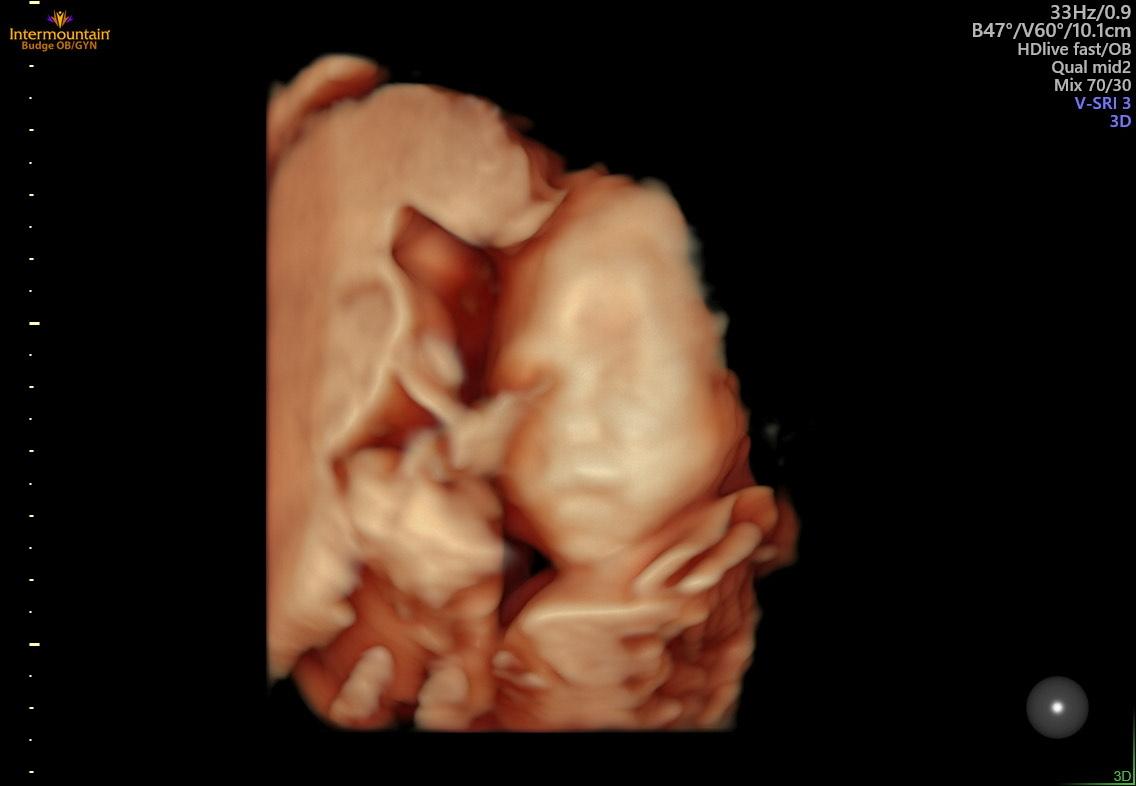

然而,在達到孕中期後,麥迪森開始有更多的發現。第二次超聲波檢查顯示她有另一個血腫,她孩子的大腦發育不正常。超聲技術人員也很難找到嬰兒的鼻骨。

在18週時,麥迪森最擔心的事情出現在母胎醫學掃描中,當時超聲技術人員在異常長的時間內保持沉默。

麥迪森的心開始跳動,因為她感到胃裡有一種下沉的感覺。沒過多久,醫生走進房間,給焦慮的父母做出了診斷:阿洛巴前腦無裂畸形 (HPE)——一種先天性疾病,嬰兒的大腦無法分為左半球和右半球。

這對夫婦得知嬰兒查理也患有多種心臟缺陷。醫生說,阿洛巴HPE的診斷是致命的。